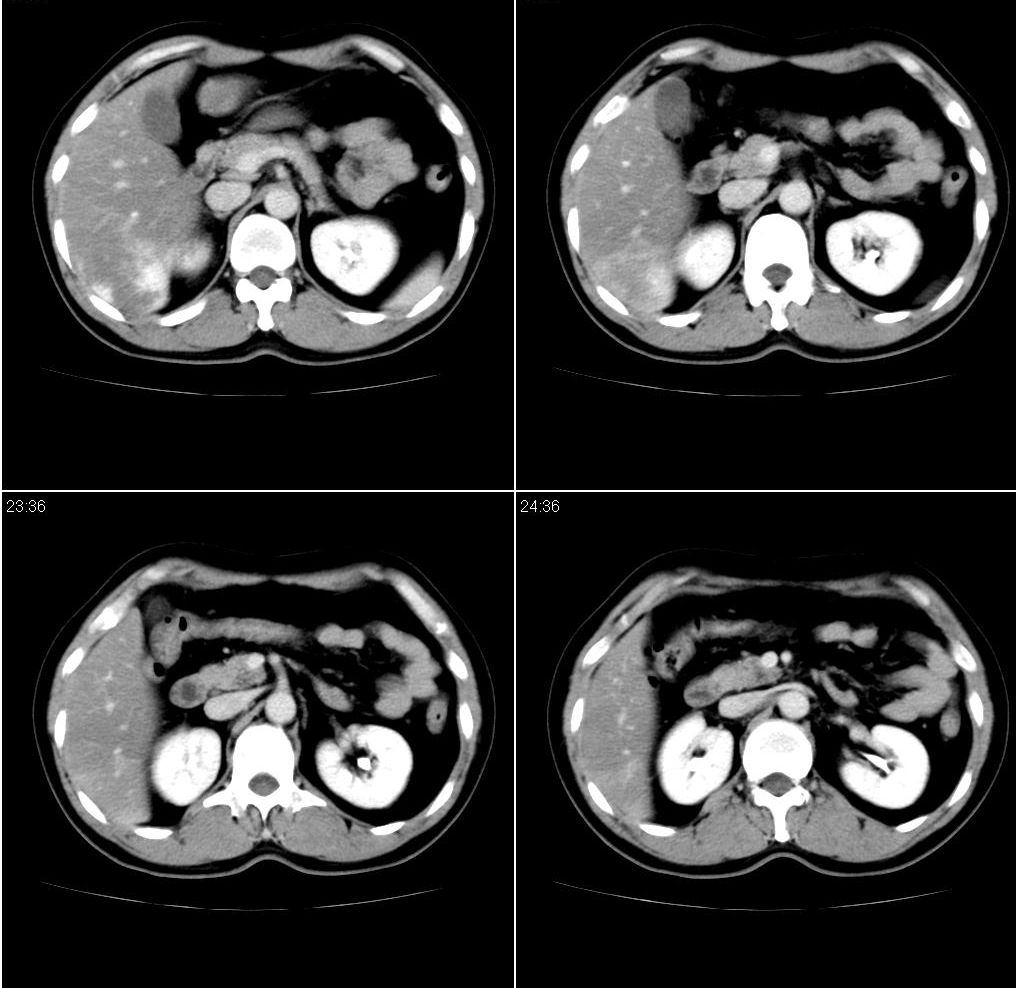

男,43岁。体检发现肝脏病变

肝局灶性脂肪肝 肝左叶外侧段占位病变,建议加强

考虑肝左叶癌并脂肪肝,肿块在脂肪肝衬托下呈高密度影,其内可见坏死灶,建议增强

肝右叶密度均匀减低,左叶增大,表面凹凸不平,内有低密度影。脾不大其密度较肝稍高。考虑1脂肪肝2肝左叶占位。建议增强。

1)局灶性脂肪肝2)肝左叶外侧段内占位,建议强化

肝局灶性脂肪肝 肝左叶外侧段1)肝海绵状血管瘤2)肝ca

肝局灶性脂肪肝 肝左叶外侧段占位病变(肝癌?),建议增强。

肝右叶密度均匀减低,左叶增大,表面凹凸不平,内有低密度影。考虑1局灶性脂肪肝 2肝左叶占位。建议增强。

下缘与胃窦关系密切,会不会是来源于胃的间质瘤??

增强后诊断很明确了,缓慢结节样强化:肝内多发血管瘤